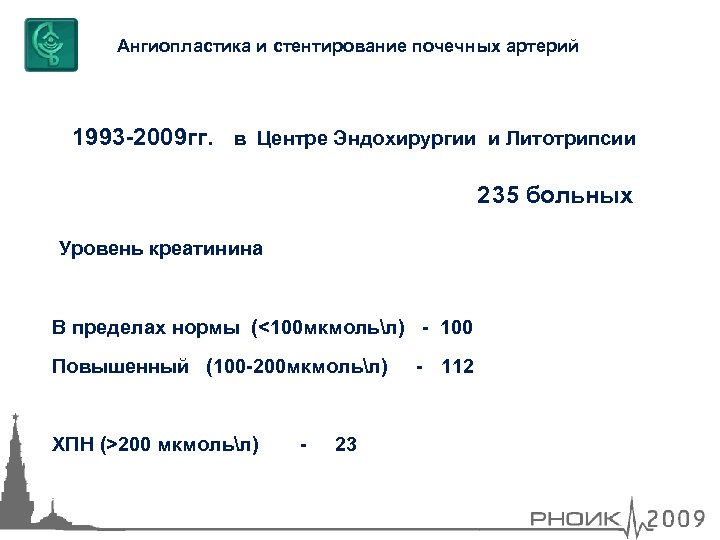

Ангиопластика и стентирование почечных артерий 1993 -2009 гг. в Центре Эндохирургии и Литотрипсии 235 больных Уровень креатинина В пределах нормы (<100 мкмольл) - 100 Повышенный (100 -200 мкмольл) ХПН (>200 мкмольл) - 23 - 112

Ангиопластика и стентирование почечных артерий 1993 -2009 гг. в Центре Эндохирургии и Литотрипсии 235 больных Уровень креатинина В пределах нормы (<100 мкмольл) - 100 Повышенный (100 -200 мкмольл) ХПН (>200 мкмольл) - 23 - 112